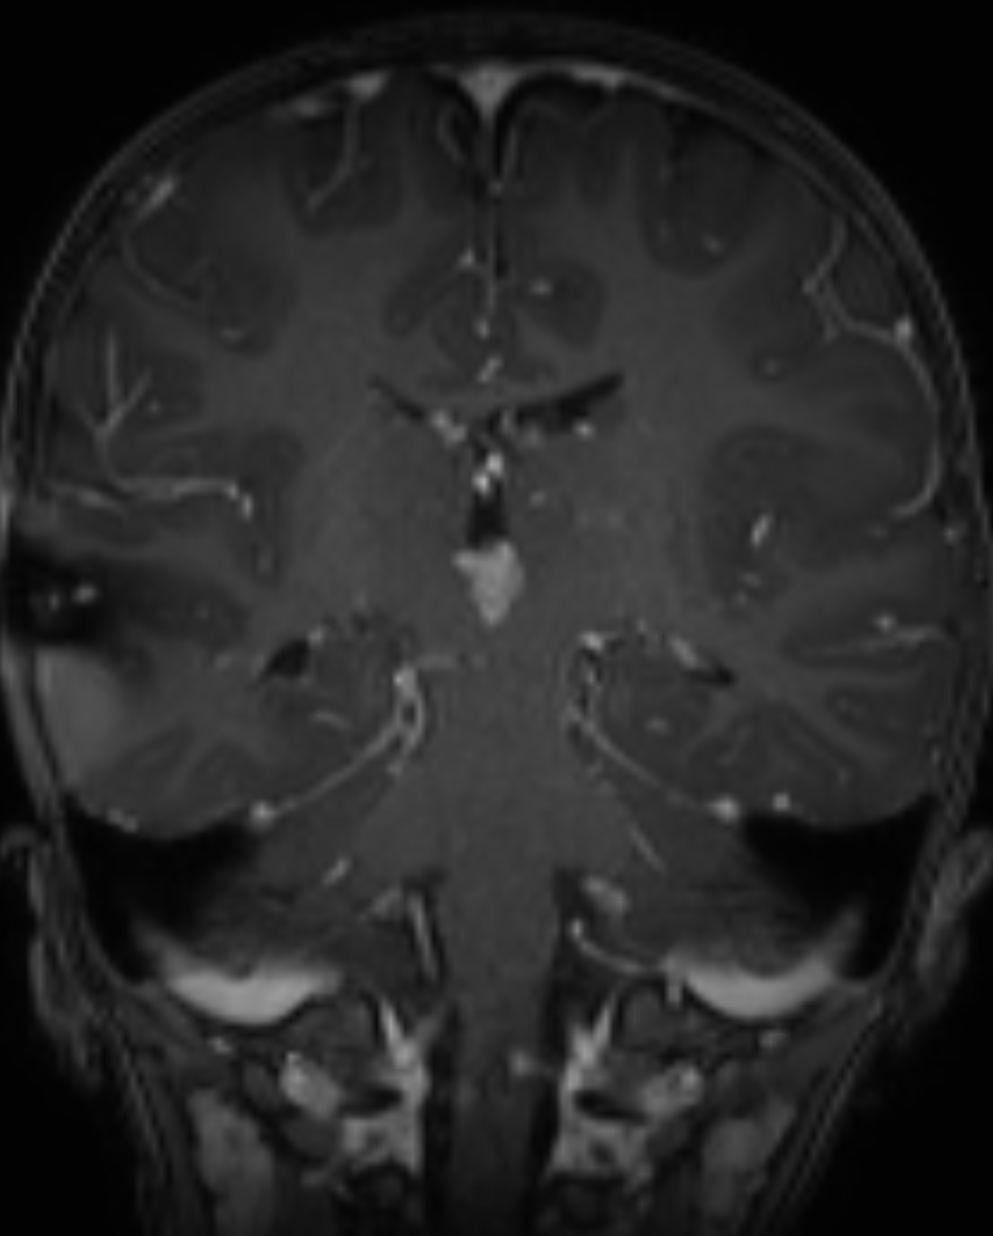

Der Goldstandard in der Darstellung von Plexuspapillomen ist die MRT Bildgebung. Im MRT zeigen sich Plexuspapillome als gut definierte extra-axiale Läsion mit Farnkrautwedel-artigen Projektionen, mit einer Kontrastmittelaufnahme und ohne Invasion des Gehirnparenchyms. In seltenen Fällen können Plexuspapillome nur wenig oder kein Kontrastmittel aufnehmen[^3].

Coronares MRT Bild eines Patienten mit einem Plexuspapillom im dritten Ventrikel.Coronares MRT Bild eines Patienten mit einem Plexuspapillom im dritten Ventrikel.

Coronares MRT Bild eines Patienten mit einem Plexuspapillom im dritten Ventrikel.